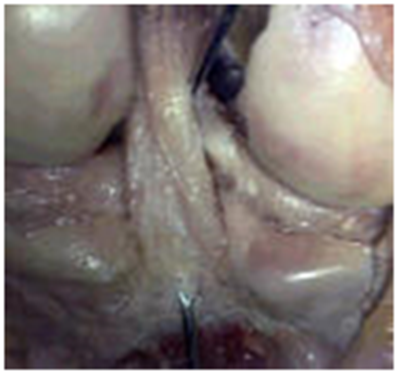

We have shown the surgical technique with flip cutter retrograde of arthrex for PCL reconstruction we do it in all four patients (Figure 8A & 8B). The four male patients between 20 and 36 years, mean age 26 years, left and right knee, both are with combined ACL injury and two with isolated PCL. In combined injuries was performed reconstruction in two stages, in a first stage ACL arthroscopic repair and 4 months PCL arthroscopic reconstruction. The results of this surgery are not as reproducible as in the LCA and may be a slight residual instability that has no clinical impact. For these reason, only patients that have extreme instability can be operated.

Figure 8a Flip rotating cutter retrograde.

Figure 8b Flip Cutter.